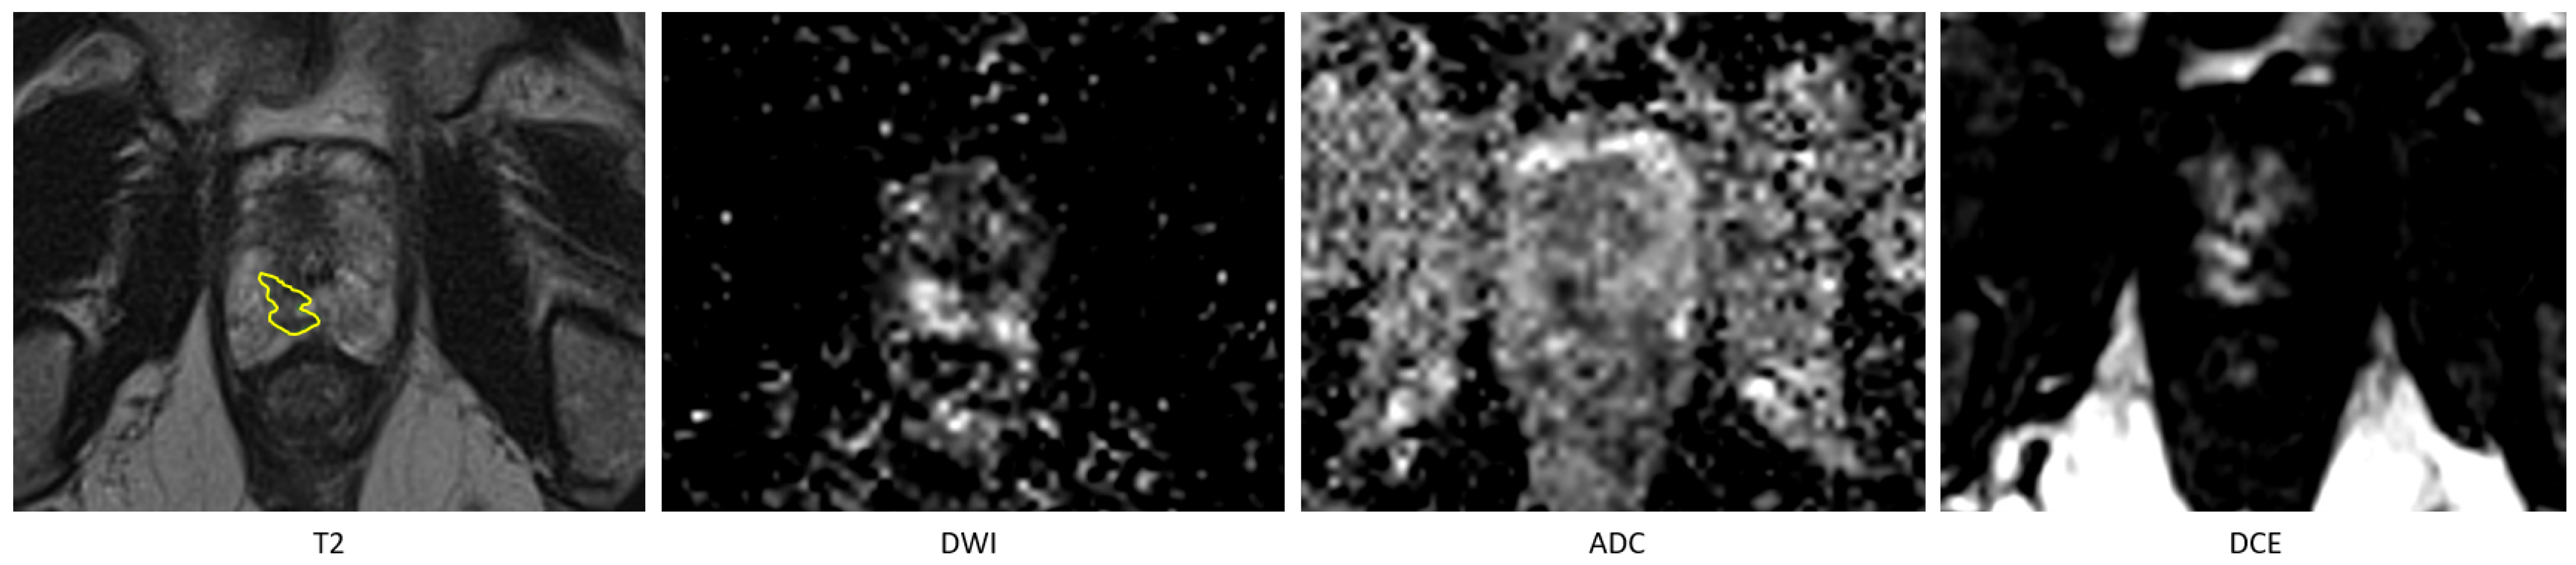

3.1. Tumor Detection

In the comparison between the radiologist and the fully automated AI method, a total of 175 lesions were manually annotated across the 120 included patients. The fully automated AI method achieved a recall of 0.74 and a precision of 0.76 in detecting these lesions. When comparing the radiologist’s segmentations to those of the AI-assisted model, the AI-assisted method demonstrated substantial improved performance, achieving a recall of 0.95 and a precision of 0.94. Detailed metrics are provided in Table 1. An example of missed lesion (false negative) by the fully automated AI method is demonstrated in Figure 2.

Figure 2. An example of missed lesion (false negative) by the fully automated AI method, where lesion is annotated by the radiologist (in yellow) on T2 hypointense area in the peripheral zone in the right apex with corresponding high signal on the high-B-value DWI and low signal on the ADC and on the DCE early enhancement.